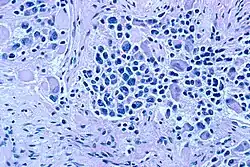

| Microscopic view of a typical neuroblastoma with rosette formation | |

On microscopy, the tumor cells are typically described as small, round and blue, and rosette patterns (Homer Wright pseudorosettes) may be seen. Homer Wright pseudorosettes are tumor cells around the neuropil, not to be confused with a true rosettes, which are tumor cells around an empty lumen.[29] They are also distinct from the pseudorosettes of an ependymoma which consist of tumor cells with glial fibrillary acidic protein (GFAP)–positive processes tapering off toward a blood vessel (thus a combination of the two).[30] A variety of immunohistochemical stains are used by pathologists to distinguish neuroblastomas from histological mimics, such as rhabdomyosarcoma, Ewing's sarcoma, lymphoma and Wilms' tumor.[31]